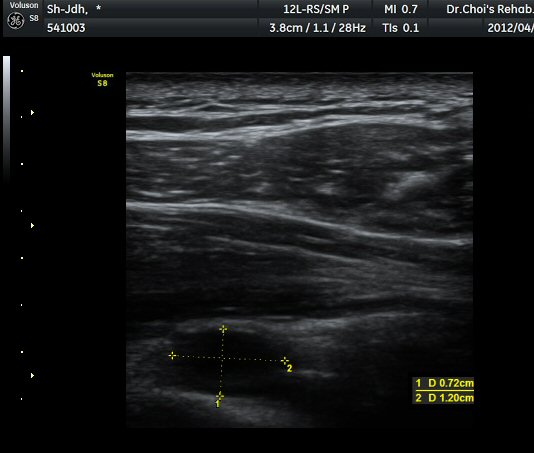

ÃÊÀ½ÆÄ °Ë»ç ; ³¶Á¾ÀÇ Å©±â°¡ Å©°Ô(1/5) ÁÙ¾îµë

ÈíÀÎ Àü ³¶Á¾ÀÇ Å©±â

1345022819_f82d3fc0_IMG_20120424_2.jpg

ÈíÀÎ 5ÀÏ ÈÄ ³¶Á¾ÀÇ Å©±â

1345022819_8d719317_para_6.jpg